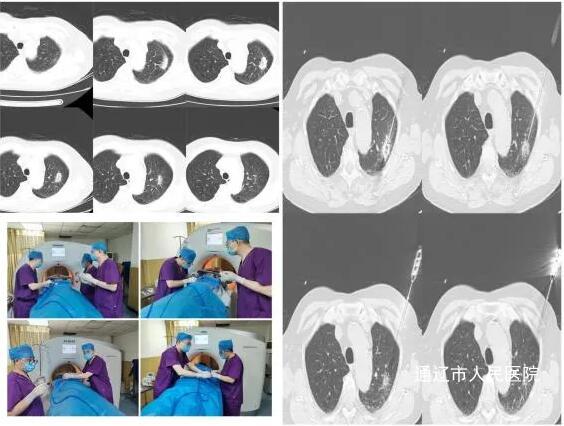

近日,我院阚庆玲主任医师团队成功为一名76岁高龄高危肺结节患者实施了CT引导下经皮肺结节微波消融治疗。

患者王某,76岁,4年前体检胸部CT提示左肺上叶磨玻璃结节,大小约2.5X2.0CM;今年6月复查发现磨玻璃结节增大并存在变性成分,影像提示高危结节。考虑其为高龄且手术不耐受患者,遂为最大程度减少其肺部损伤,科室决定行肺部结节微波消融微创术。

手术在麻醉科刘石磊主任团队全程静脉麻醉及柳晨教授、阚庆玲主任的指导下,由技师王芳科,主治医师闫强、孙雨主副配合顺利为患者实施了肺结节微波消融治疗。 为让患者尽快康复,呼吸与危重症医学科何佳木、赵翠翠医护团队单独为患者划分了病区。经数日精心护理下,患者恢复良好,现已顺利出院。术后1月余,患者复查CT,病灶消融范围足够,无任何并发症,消融效果良好。